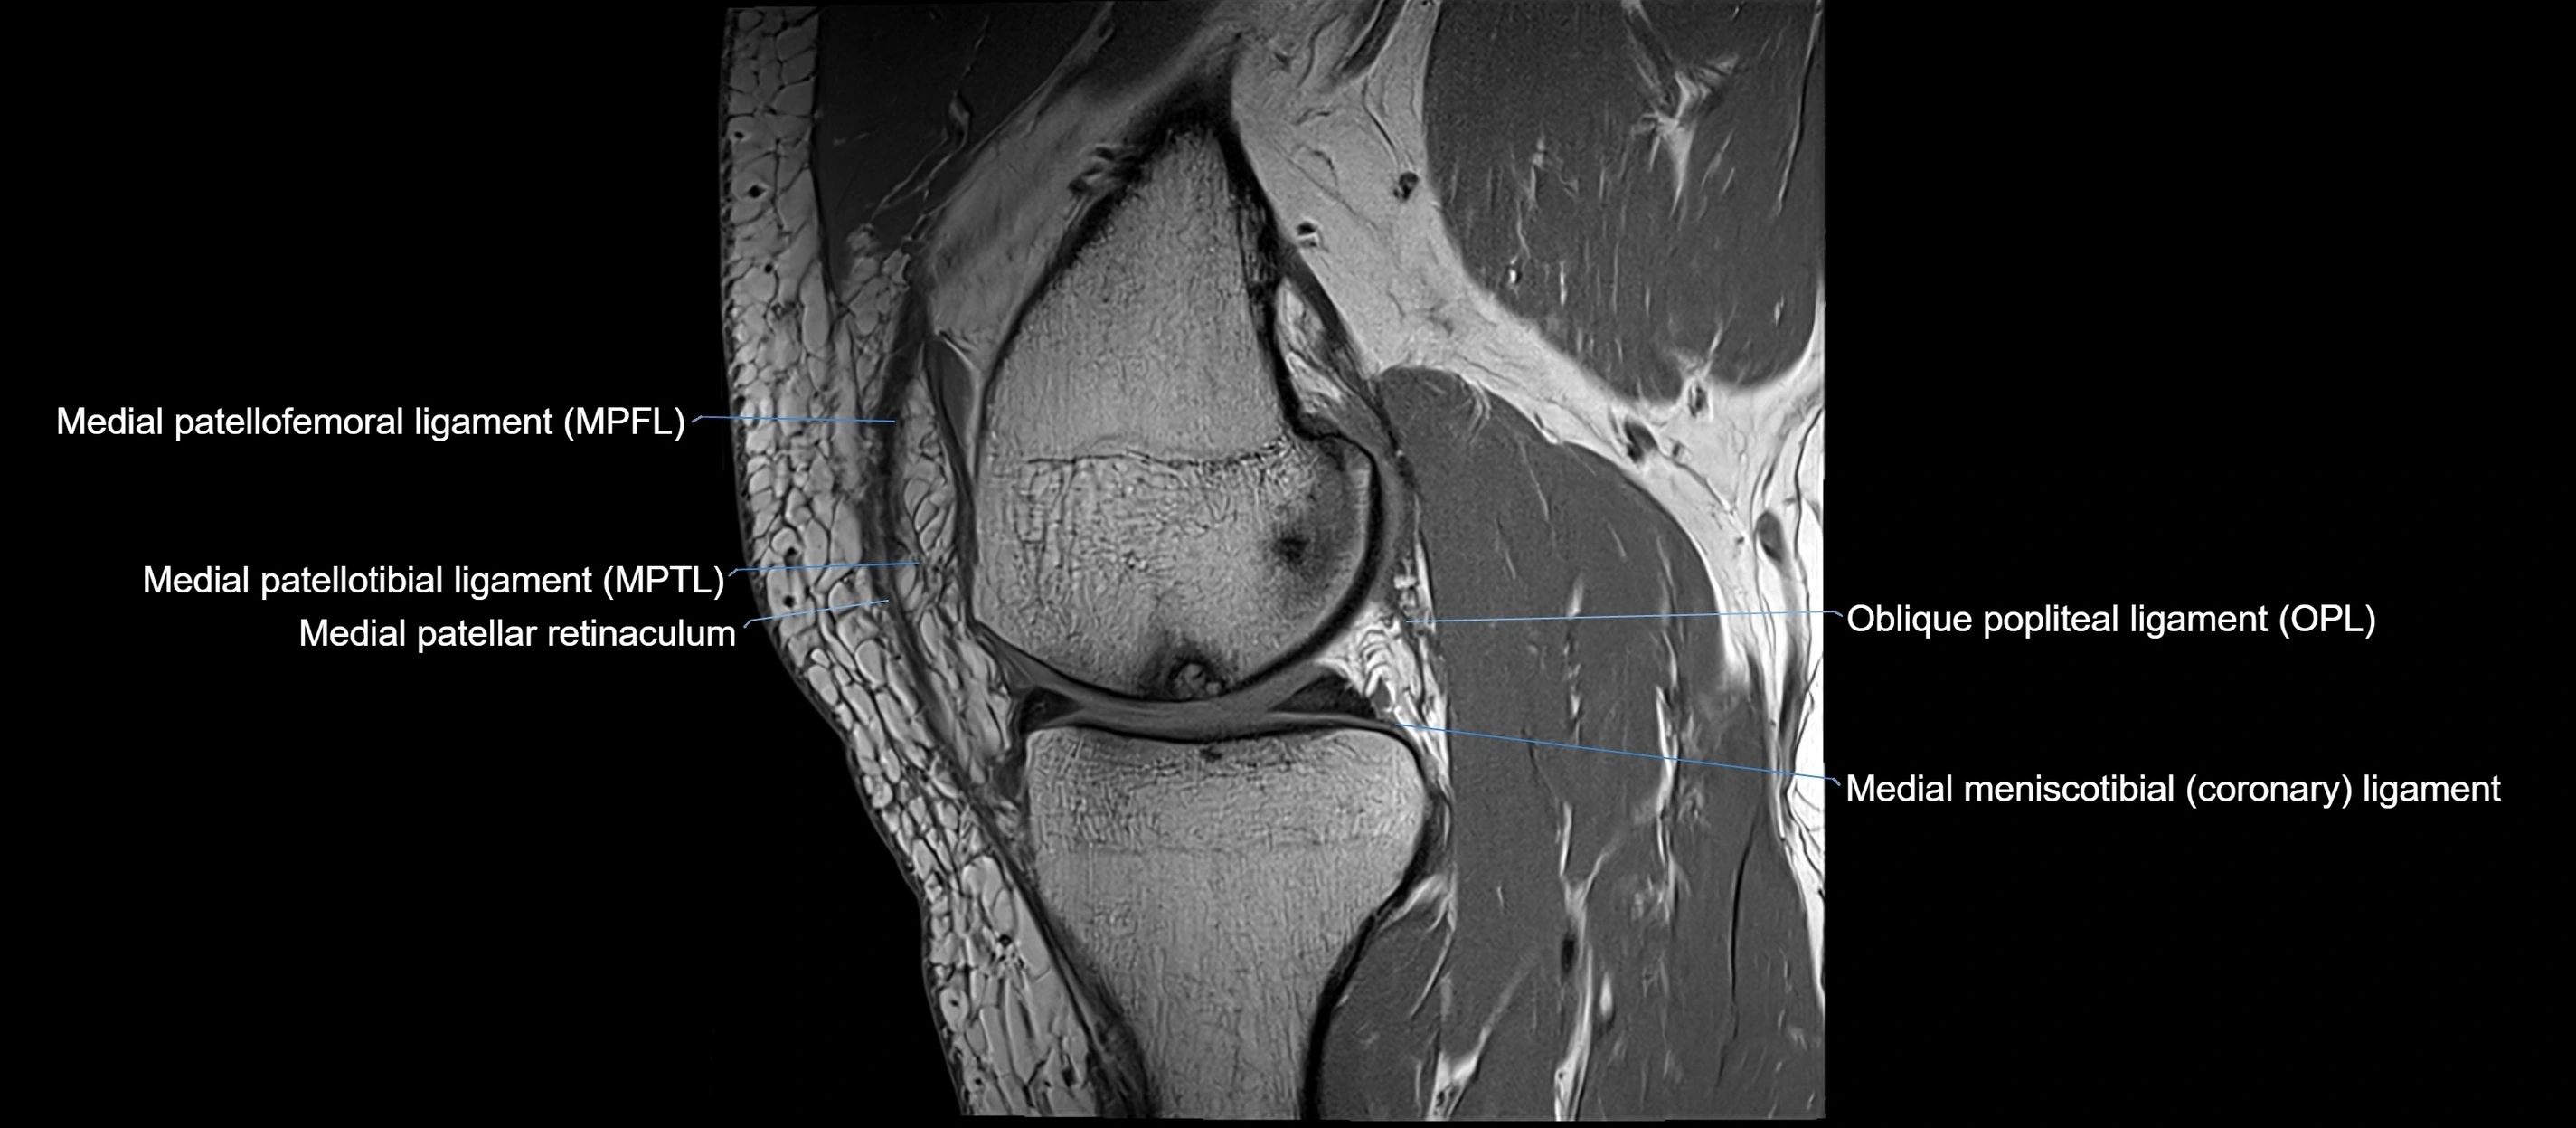

MRI images

image